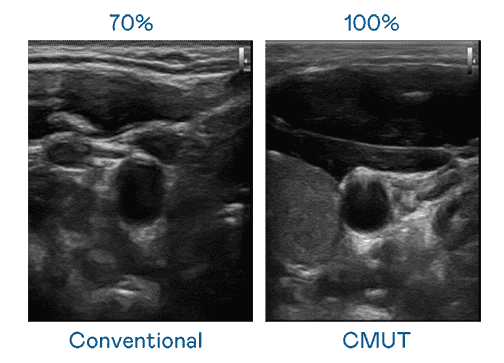

CMUT 技术是一种用电容式微机电元件来产生超音波讯号的技术。。。与传统 PZT 压电式技术相比,,,,CMUT 频宽增加 30%,,,更宽频的超音波讯号让影像解析度大幅提升,,,是实现高影像品质医疗超音波扫描、、、促进精准医疗发展的关键技术。。

超音波影像的解析度高低,,首先取决于探头能发出的讯号频宽。。。。尊时凯龙 CMUT 可提供高清晰的超音波讯号,,,,提供高频宽、、高灵敏度、、、影像纹理细节更高的超音波影像,,,,协助医护人员缩短影像判读时间及利用精准的医疗影像进行诊断。。